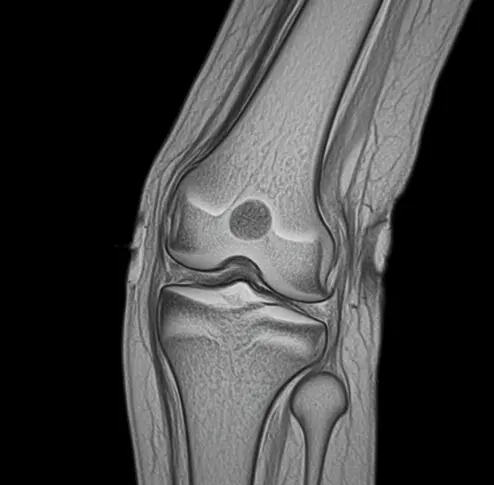

무릎 관절 MRI (Magnetic Resonance Imaging)는 강력한 자기장과 라디오파를 이용하여 무릎 내부의 뼈, 연골, 인대, 근육, 힘줄 등의 연부 조직을 고화질 단면 이미지로 만들어내는 진단 검사 방법입니다.

단순 X-ray로는 확인하기 어려운 미세한 연골 손상, 인대 파열, 물혹, 염증 등을 명확하게 진단할 수 있어, 통증의 정확한 원인 파악과 그에 맞는 적절한 치료 계획을 세우는 데 결정적인 역할을 합니다. 오래 지속되는 통증이나 심한 외상 후 상태를 확인할 때 특히 필요합니다.